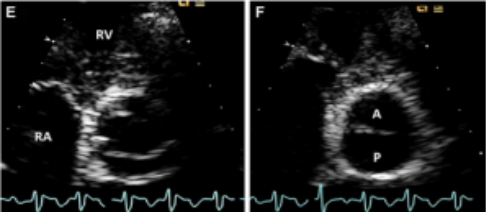

正常主动脉瓣由3个半月瓣组成,称三叶式主动脉瓣(tricuspid aortic valve, TAV),根据瓣膜位置及冠状动脉开口可将其分为左、右和无冠状动脉瓣。而BAV因主动脉瓣发育异常导致相邻两个半月瓣形成融合瓣,部分融合瓣上可见融合嵴,使瓣叶不对称。

Sievers分型

Sievers分型广泛应用于临床,根据融合嵴的数量将BAV分为3型:Type 0型(无嵴)、TypeⅠ型(1个嵴)和TypeⅡ型(2个嵴),其中最常见的是TypeⅠ型,约占90%。根据嵴的空间位置又分为左右冠窦融合型(RL型)、右无冠窦融合型(RN型)、左无冠窦融合型(LN型),其中RL型最常见,约占80%。

最新国际共识认为仅基于外科角度的Sievers分型仍有局限性,因此新的分型为:融合型、双窦型和部分融合型。其中融合型最常见,占90%~95%,相当于TypeⅠ型。双窦型BAV并不常见,占5%~7%,由大小、形状大致相同的两个瓣叶构成,分前侧对侧表型和前后表型(图b)。部分融合型的流行率尚不清楚,表现为典型的三叶瓣膜,但在连合底部可见<50%的瓣尖融合。至于Sievers分型中的Type Ⅱ型,共识认为称单叶瓣较为合适。